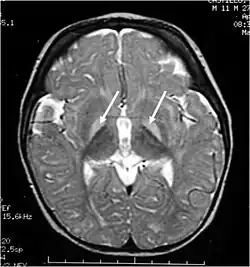

Querníctero ou encefalopatia bilirrubínica é uma lesão cerebral causada pela deposição de bilirrubina não conjugada nos gânglios da base e dos núcleos do tronco cerebral.[1]